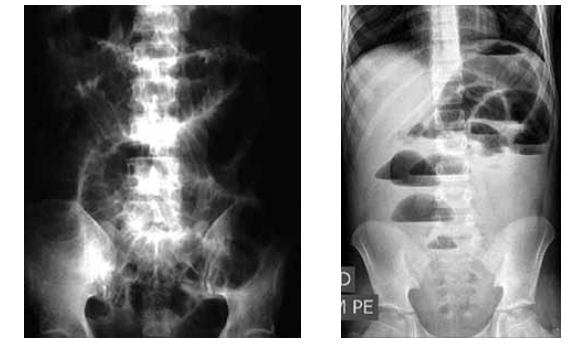

Homem de 45 anos procurou pronto-atendimento com história de náuseas, vômitos e distensão abdominal há 2 dias. Não elimina flatos ou fezes desde então. Foi submetido a uma laparotomia exploradora aos 40 anos por ferimento abdominal por arma de fogo (FAF). Foi uma operação extensa, segundo relato do paciente, em que foi removido mais de 1 metro de intestino delgado. Ao exame físico: em regular estado geral, um pouco desidratado, PA: 110 x 80 mmHg, FC: 85 bpm, RHA aumentados, abdome globoso, timpânico, globalmente doloroso, sem sinais de peritonite. Apresenta RX abdome (posição supina e ortostática) a seguir.

Enunciado 3561498-1

Qual o diagnóstico sindrômico e etiológico mais provável e a conduta inicial mais indicada?